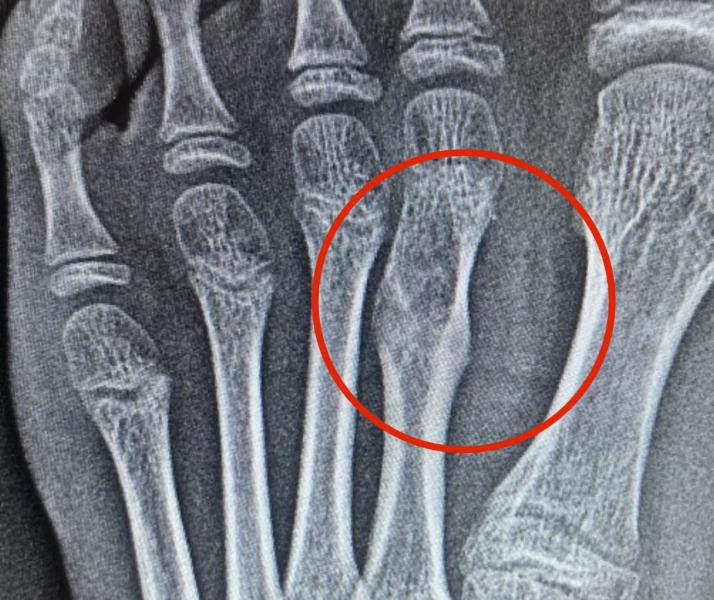

РЕБЕНКУ НУЖЕН ОРТОПЕД/ ОРТОПЕД- ОНКОЛОГ СПб , ЕСТЬ КОНТАКТЫ ?

Упала болела нога, сделали ренген на ноге растяжение, зато на второй вот такая картина , сказали есть подозрение на опухоль, нужна консультация специалиста